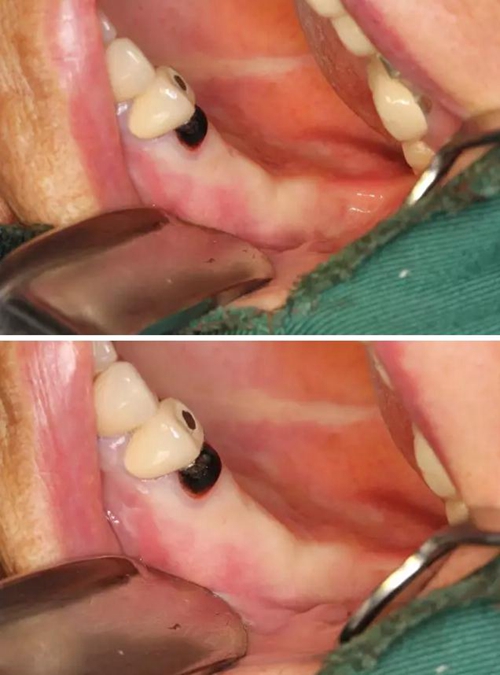

【病例分享】右上內(nèi)提+5冠延長1 梁光強